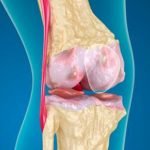

يعد مرض خشونة الركبة أو ما يعرف طبياً بمرض المفاصل التآكلي، من ضمن الأمراض التي ظهرت خلال السنوات الأخيرة وانتشرت لعدة أسباب، فهذا المرض عبارة عن تعرض الغضاريف والعظام اللينة الموجودة ما بين الأصابع والعظام لاسيما الركبة، إلى التآكل والذوبان مما يعني تعرض الركبة والعظام للخشونة بسبب كثرة الاحتكاك بين العظام دون وجود غضاريف تحميها من الاحتكاك الدائم، وهذا ينتج عنه العديد من الأعراض الخطيرة مثل:

- تورم شديد في المنطقة المصابة بالخشونة.

- ألم شديد في الركبتين ويزداد هذا الألم مع المجهود الزائد أو رفع الأغراض الثقيلة.

- احمرار في منطقة الركبة بسبب الالتهابات الداخلية بسبب ذوبان العظام اللينة والغضاريف داخل الركبة.